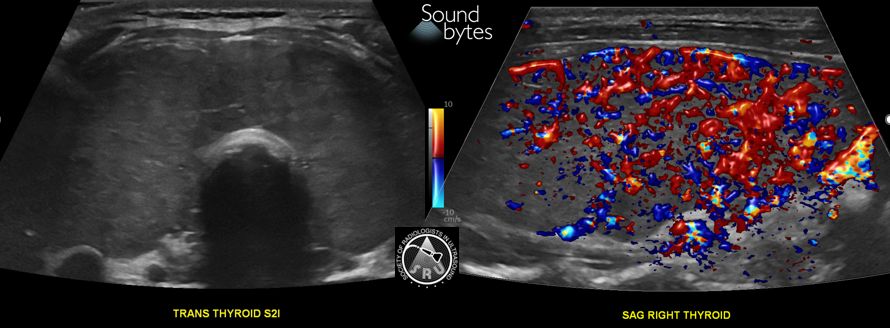

@sruradiology

SRU Radiology

1 month

Answer: Acute Thyrotoxicosis/Thyroid storm Findings: Enlarged, hypervascular thyroid gland in a patient with acute sxs. Case Courtesy of Naiim Ali, MD; U of VT #RadRes #RadInTraining #ultrasound